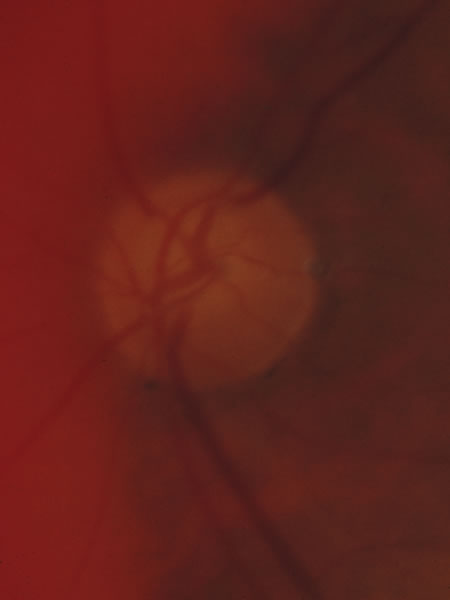

In acute angle-closure glaucoma (Fig. 33), the optic disc may swell,147–149 perhaps as a result of ischemia, but because of corneal edema and preoccupation with the angle status, it is not often seen. Even after an attack lasting several days, there is often no visual loss; the disc may remain normal appearing or may develop some degree of pallor resembling that of nonglaucomatous optic atrophy.150–152 Excavation of the disc does not seem to result from an acute attack but may result from persistent residual pressure elevation after the attack. If excavation is already present at the time that a patient presents with symptomatic angle closure, the cupping is evidence that for some time an asymptomatic, perhaps gradual, rise of intraocular pressure elevation preceded the abrupt onset of symptoms.

Fig. 33. Swollen disc tissue during an acute attack of angle closure glaucoma.